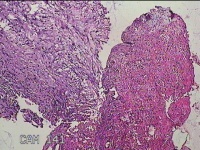

右卵巢囊肿壁

性别

女

年龄

36岁

临床诊断

右卵巢子宫内膜异位囊肿 盆腔炎性疾病后遗症

一般病史

痛经5年,加重3月。

标本名称

大体所见

灰白暗红色囊壁样组织4.5x3.3x0.8cm一堆,表面光滑,因已切开,囊内容物已流失,囊壁厚0.1cm。

图2